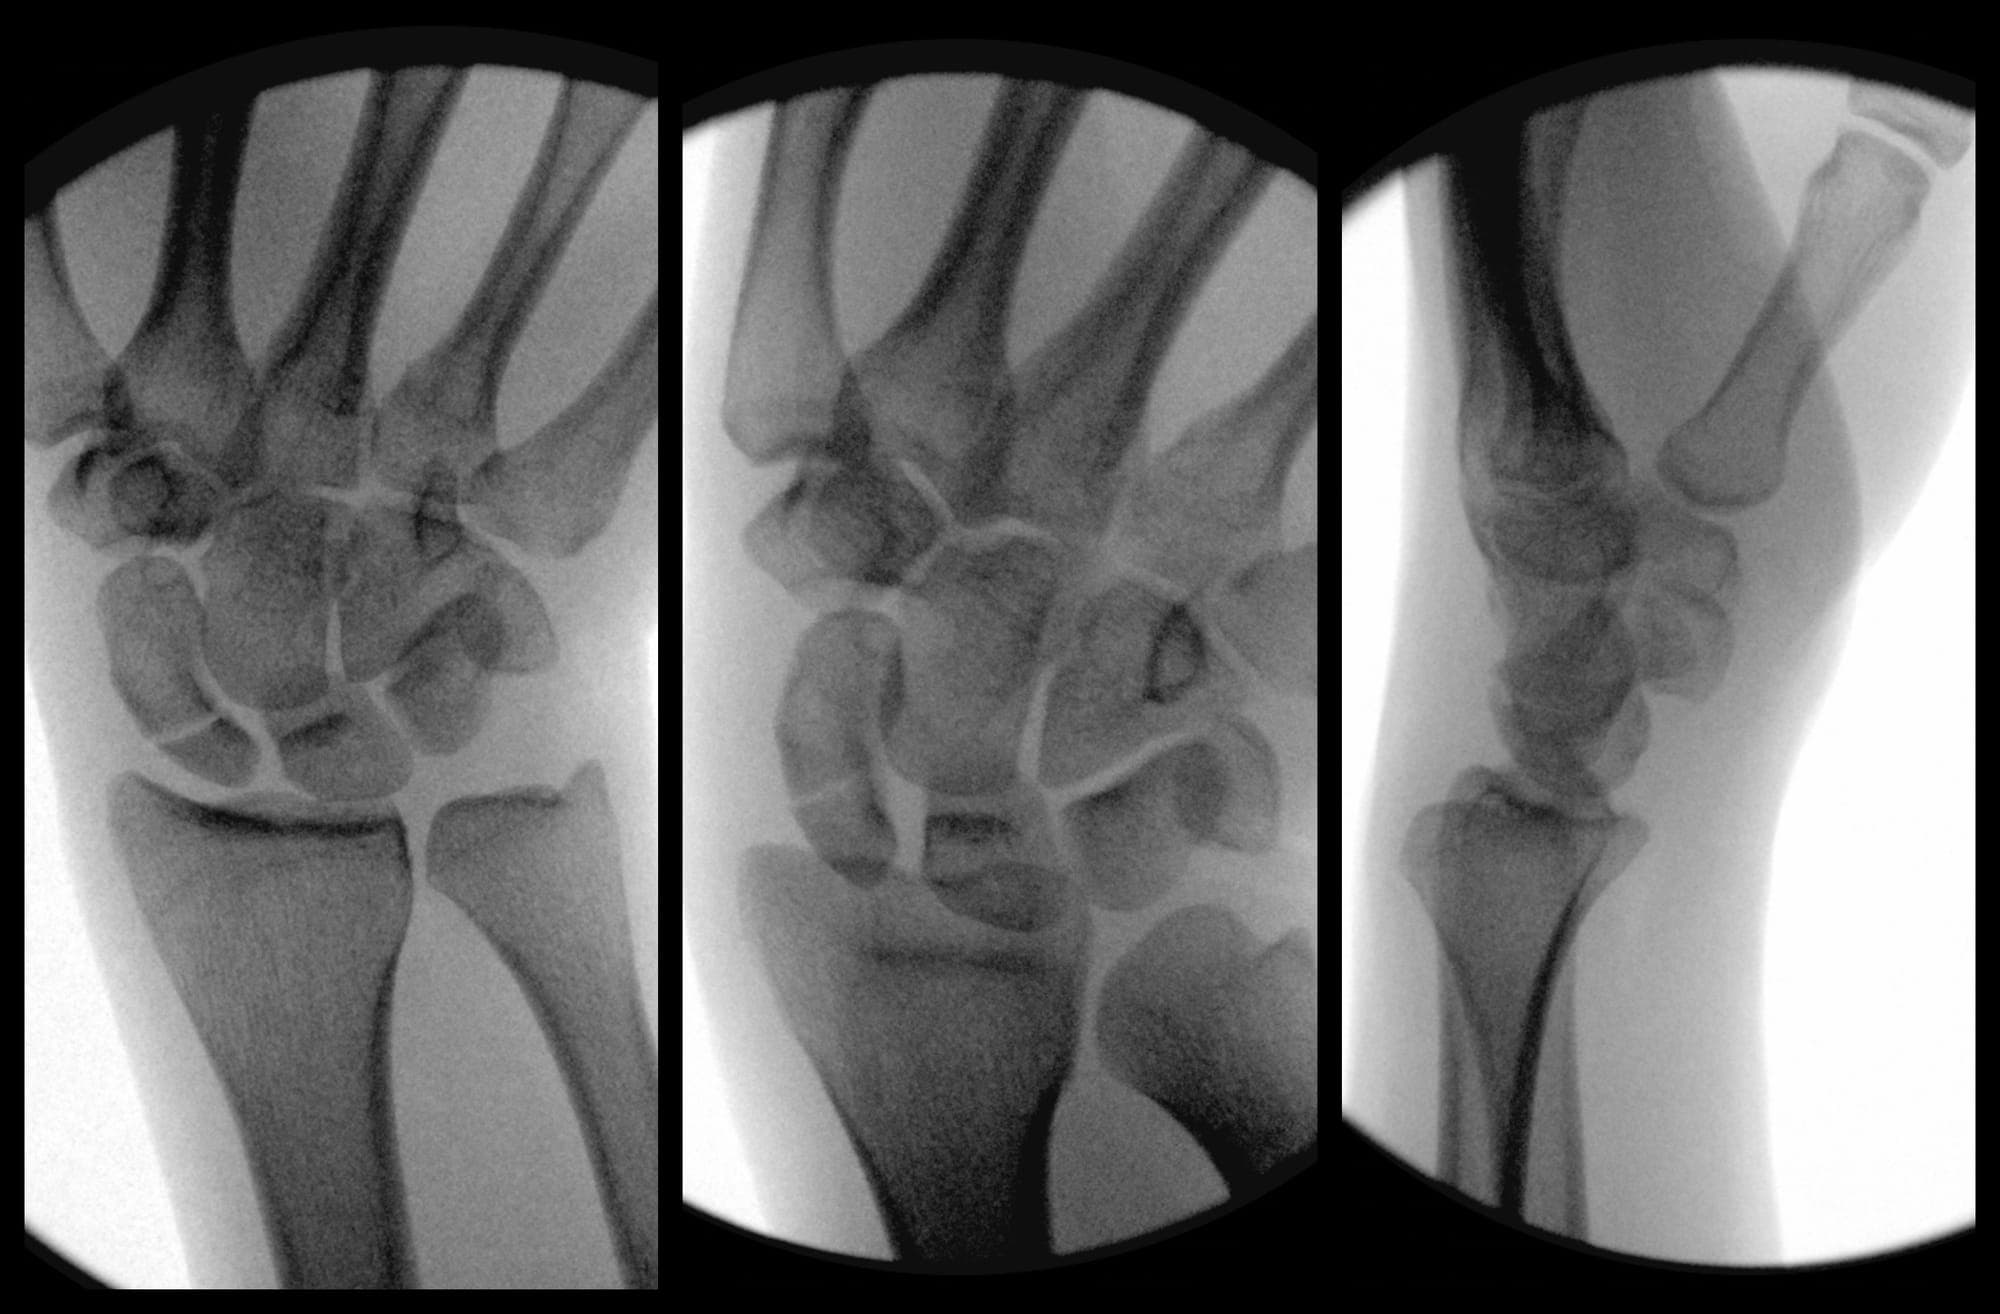

Scaphoid Fracture Fixation

David Chen, Omar Nazir, Adam Mirarchi